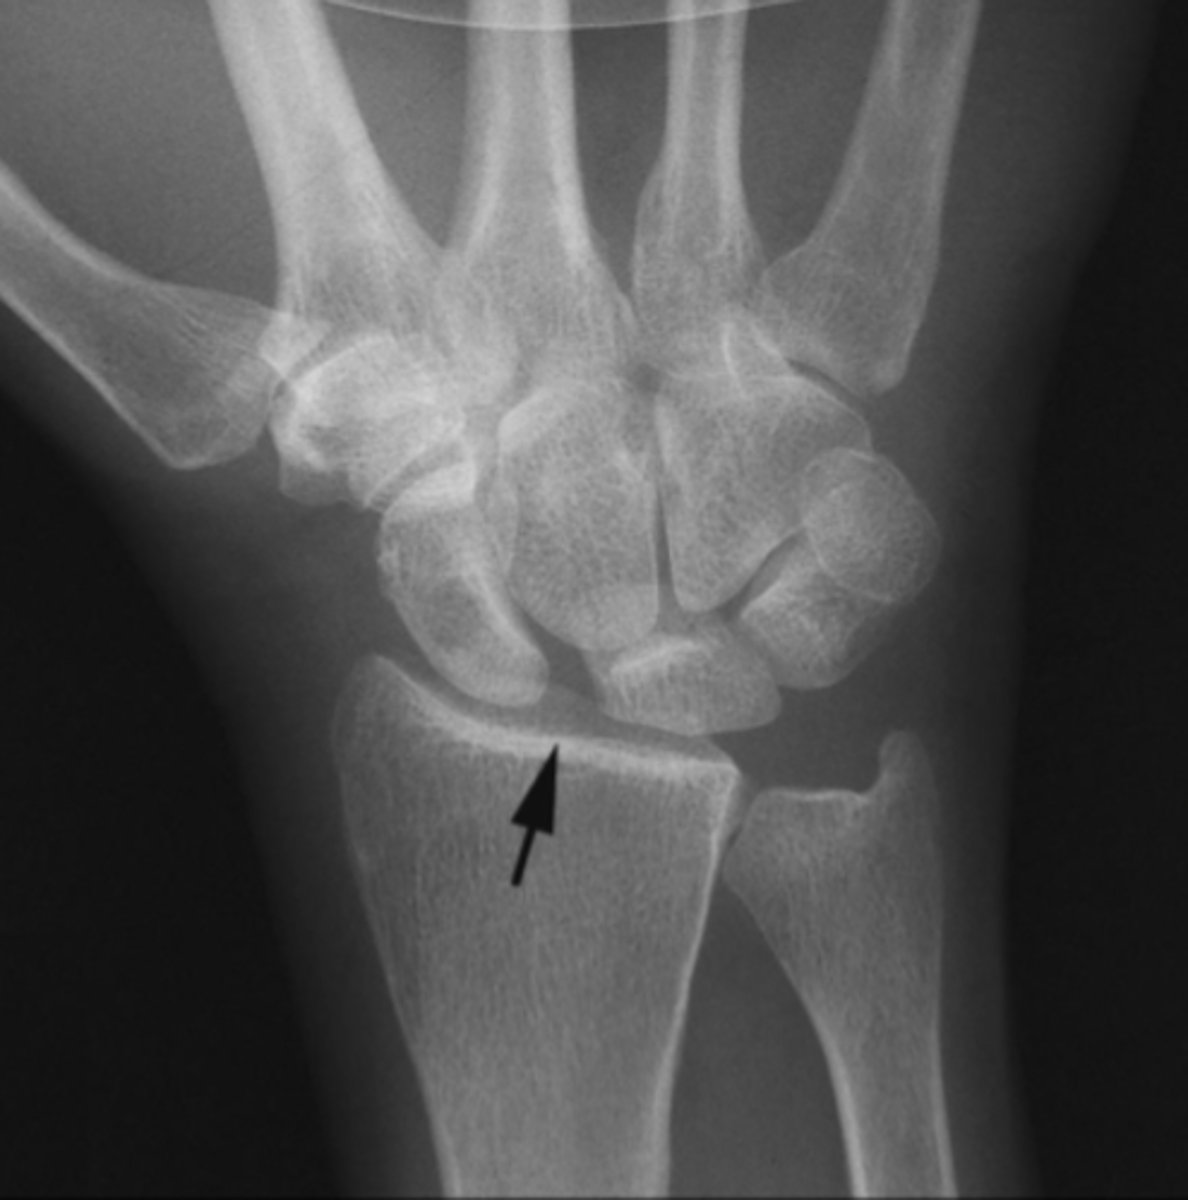

Scaphoid fracture and minor ulnar fracture

What is the issue?